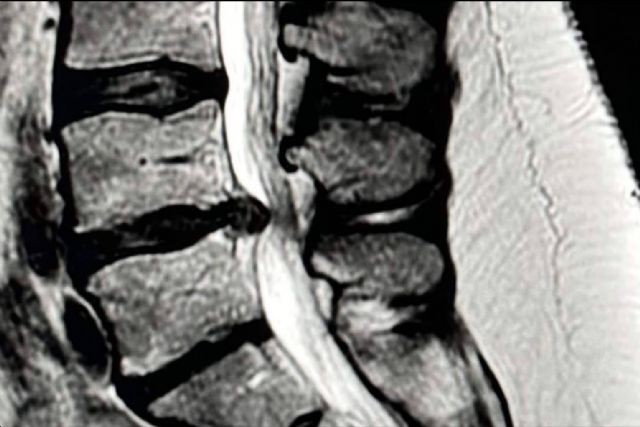

Cuando una hernia discal lumbar provoca dolor en la pierna (ciática), lo primero es intentar un tratamiento conservador: reposo relativo, medicación, fisioterapia o infiltraciones. En la mayoría de casos, estos tratamientos funcionan, pero si el dolor persiste tras unas 6–8 semanas, si aparecen síntomas neurológicos que empeoran (como pérdida de fuerza o sensibilidad) o un síndrome de cola de caballo (pérdida de control de esfínteres), puede ser necesario recurrir a la cirugía.

La microdiscectomía es la técnica de referencia desde hace años. Consiste en retirar el fragmento del disco que comprime el nervio a través de una pequeña incisión en la espalda. Es una cirugía muy segura, eficaz y con resultados predecibles a largo plazo. Una de sus grandes ventajas es que sirve para la mayoría de tipos de hernias discales y los cirujanos tienen una amplia experiencia en ella. La parte menos favorable es que, aunque se considera mínimamente invasiva, implica una mayor manipulación de los músculos de la espalda que otras técnicas más modernas.

La discectomía endoscópica es más reciente y se realiza introduciendo una cámara a través de pequeñas incisiones. Esto nos permite trabajar con mínima agresión sobre los tejidos y visualizar la cirugía en una pantalla. Los resultados en cuanto a alivio del dolor y recuperación funcional son iguales a los de la microdiscectomía, pero con algunas ventajas: menos sangrado, menos dolor después de la intervención, cicatrices más pequeñas y una recuperación más rápida. El inconveniente es que requiere una curva de aprendizaje mayor y, en algunos casos, la cirugía puede durar algo más.

En este nivel, algunas técnicas endoscópicas pueden resultar especialmente útiles, ya que evitan ciertos obstáculos anatómicos que pueden hacer más difícil el acceso. Tanto la microdiscectomía como la endoscopía ofrecen buenos resultados, y la elección depende de la anatomía del paciente y de la preferencia del cirujano.